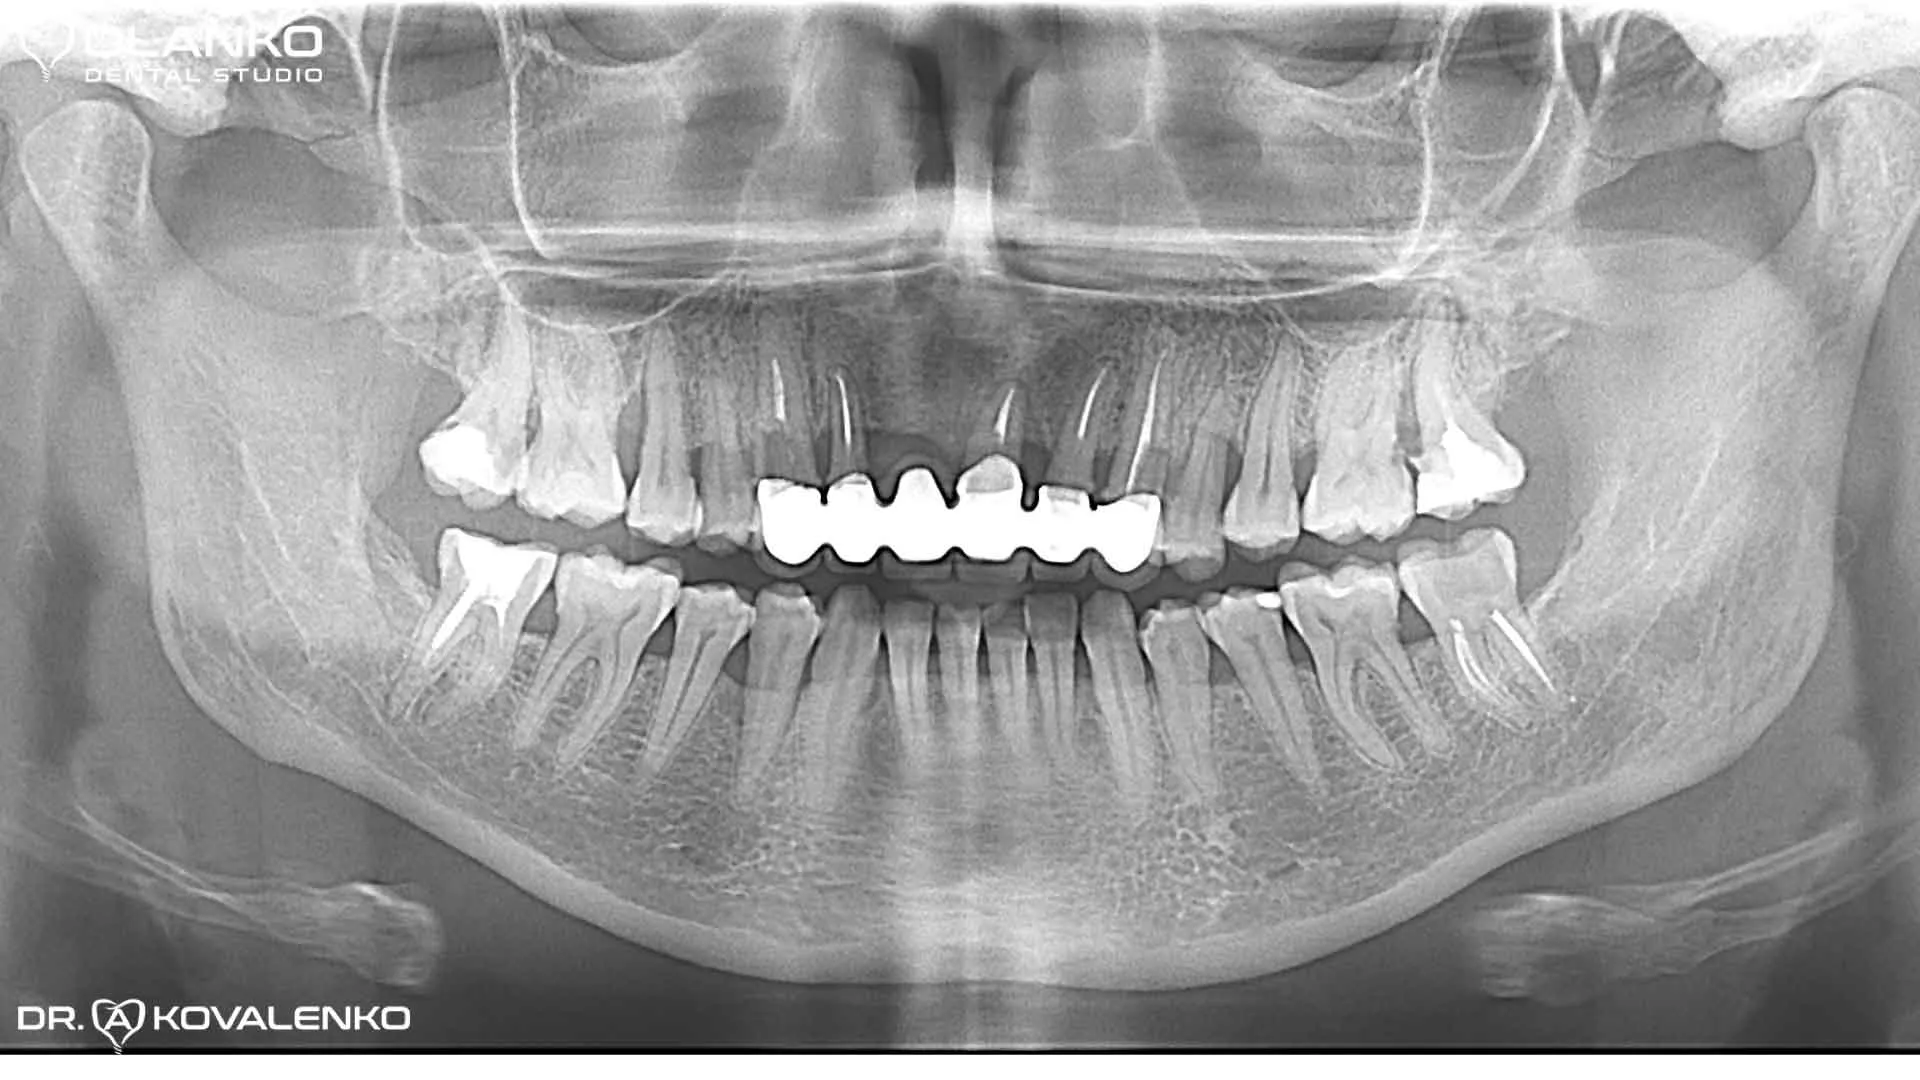

Контрольний панорамний рентген знімок після закінчення протезування на імплантатах

Видалили 5  зубів з одномоментною імплантацією, кістковою та ясеневою пластикою. Встановлено чотири зубних імплантати Straumann Roxolid SLA. Через 4 місяці проведено протезування, на імплантати встановлений безметаловий мостовидний протез з діоксиду цирконію.